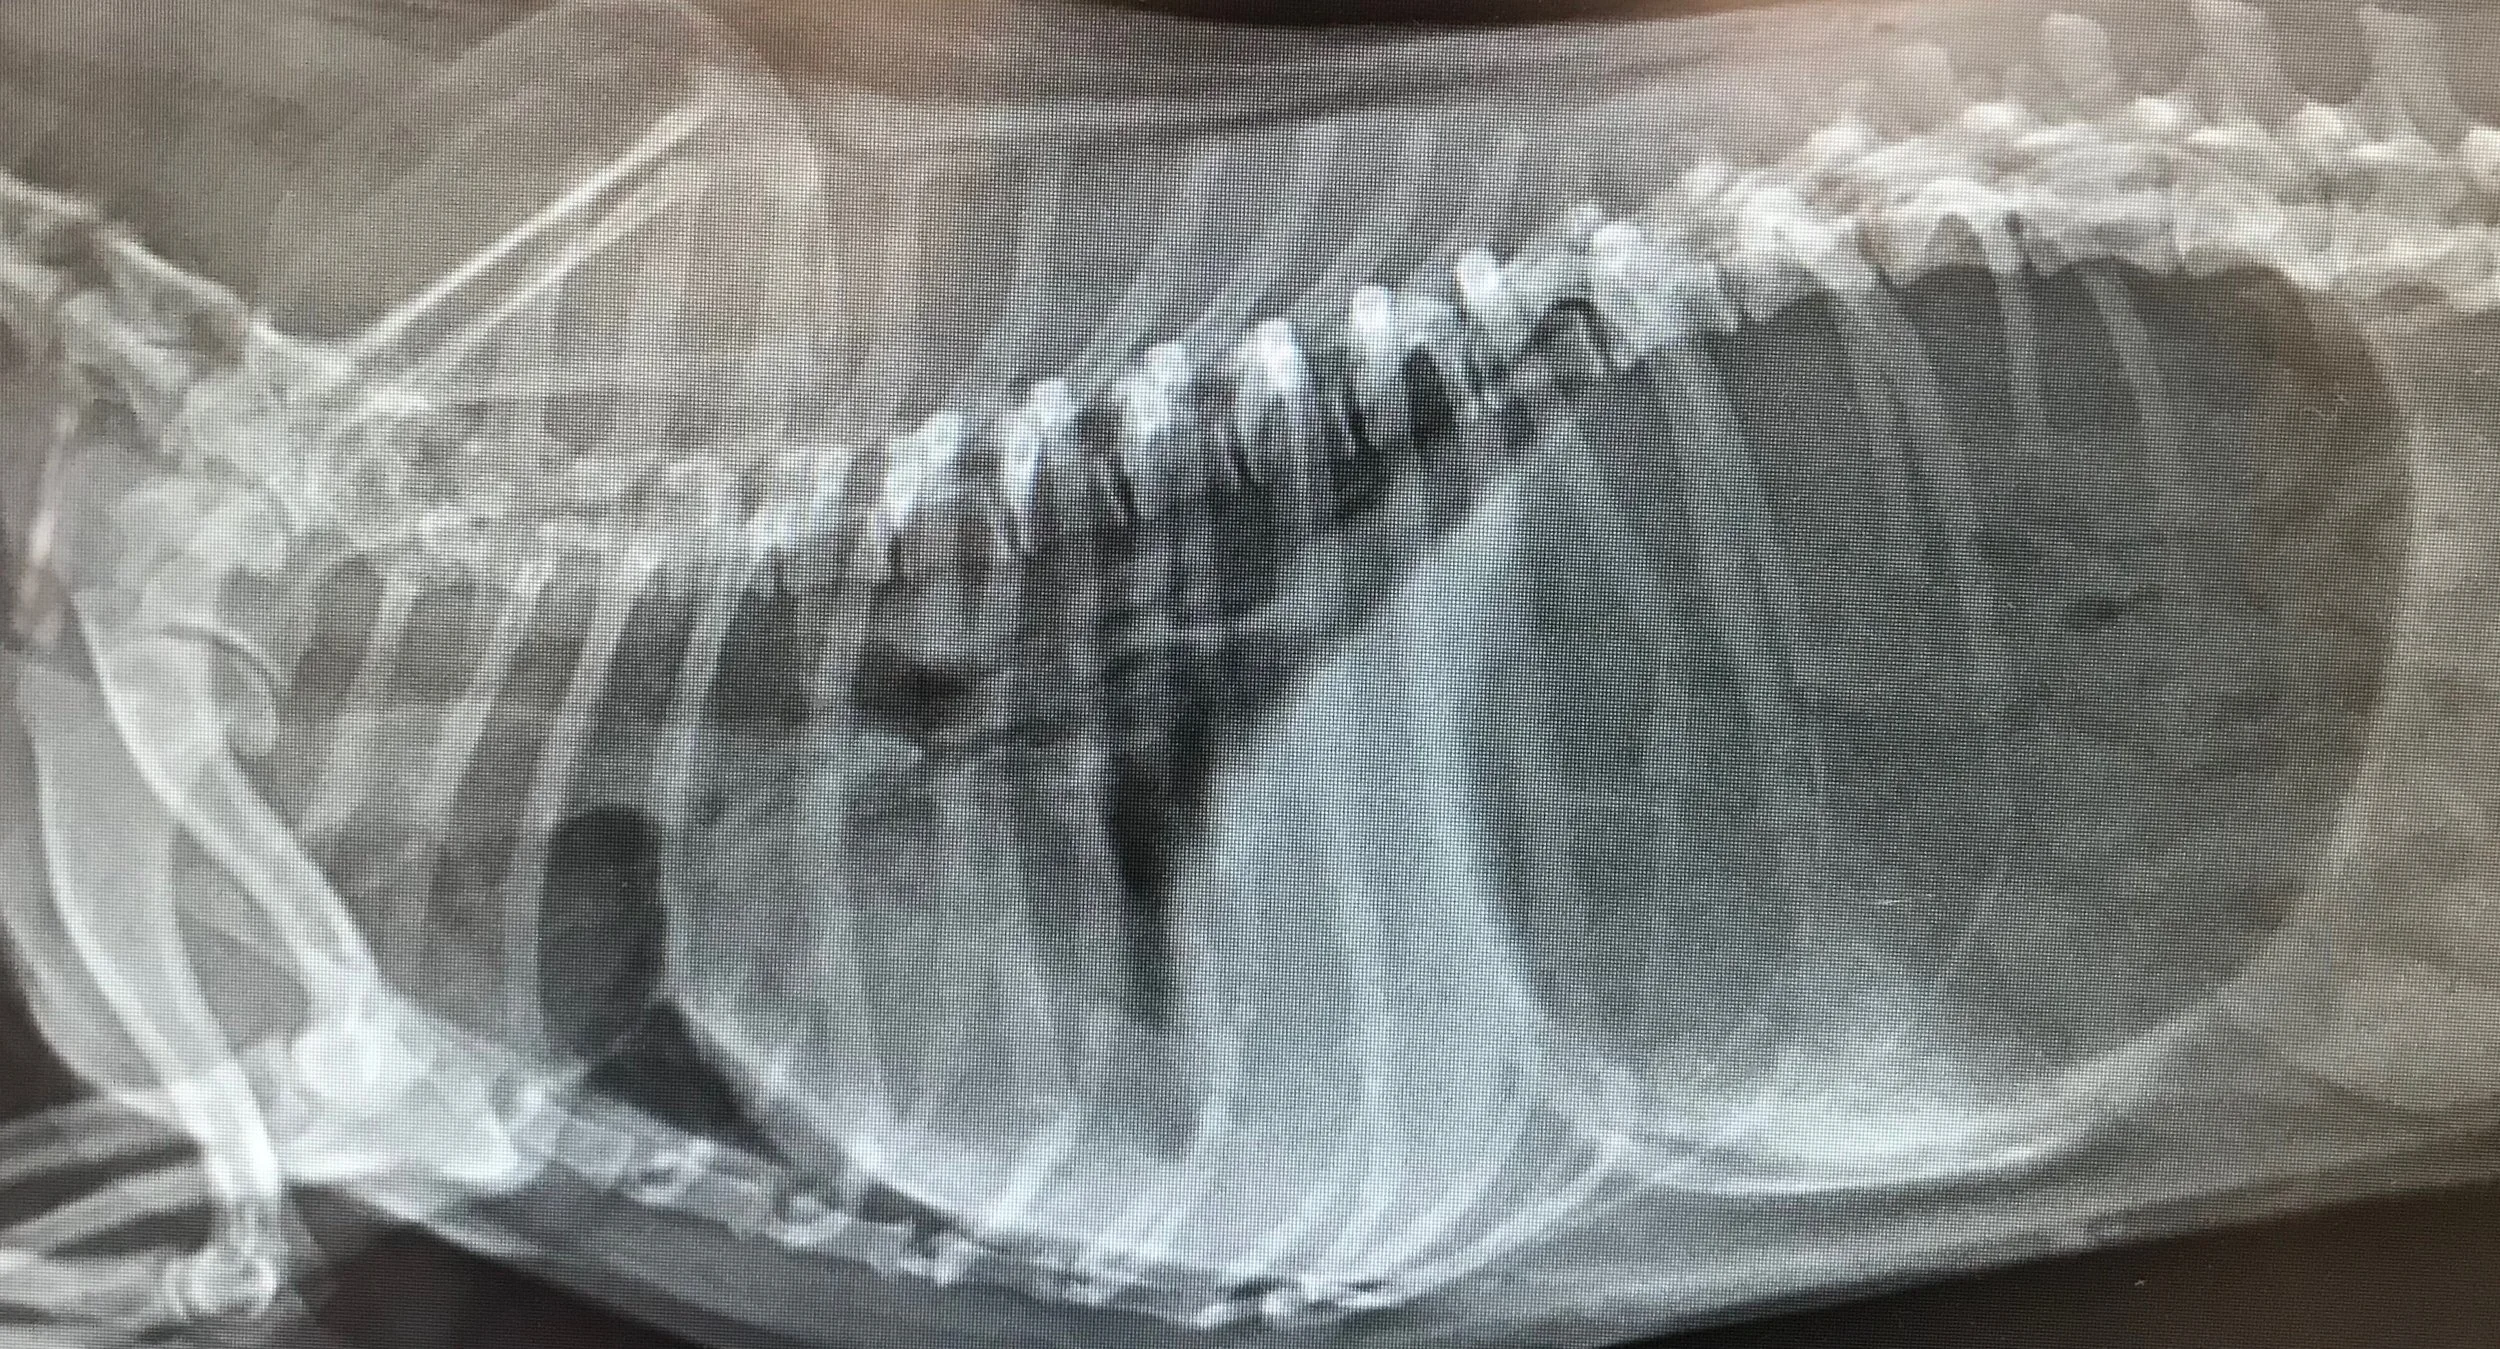

Read MoreI examine Patience and note that she is very depressed, weak and lying quietly on the exam table. Not typical behavior for a 12-week-old puppy.

Read MorePatient is a canine (dog), female, spayed, five-year-old schnauzer. The owner brought the dog in because she was urinating all over the house. The owner said that Snickers had been urinating in the house, very frequently and struggling a little when urinating.